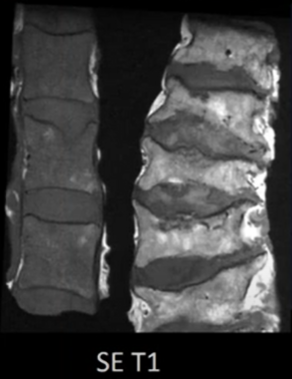

Scanner double énergie et pathologies osseuses des tissus mous

VANDE BERG B. & KIRCHGESNER T. – UCL

Conférence du jeudi

Année académique 2021-2022